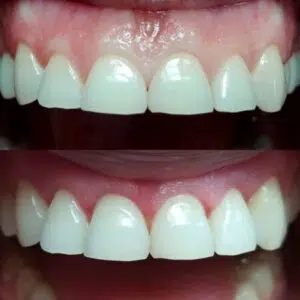

Gingiwoplastyka to procedura chirurgiczna, która polega na modelowaniu i konturowaniu dziąseł w celu poprawy estetyki uśmiechu. Zabieg ten jest bezkrwawy, bezpieczny i bezbolesny, a jego efekty są natychmiastowe i trwał

Zalety Gingiwoplastyki

- Poprawa Estetyki Uśmiechu: Korekta linii dziąseł znacząco poprawia estetykę uśmiechu, czyniąc go bardziej harmonijnym i atrakcyjnym.

Gingiwoplastyka to efektywny sposób na poprawę estetyki uśmiechu i zwiększenie pewności siebie. W naszej klinice dbamy o to, aby każdy zabieg był przeprowadzony z najwyższą precyzją i dbałością o komfort pacjenta. Dzięki nowoczesnym technologiom i doświadczeniu naszych specjalistów, możemy zapewnić pacjentom piękny i zdrowy uśmiech.